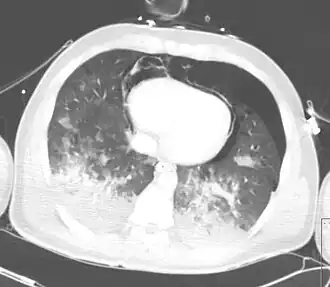

Наряду с травматическим двухсторонним гемопневмотораксом, пневмоперикардом и пневмомедиастинумом, визуализируются распространённые зоны консолидации в нижних долях обоих лёгких, обусловленные контузией.Наряду с травматическим двухсторонним гемопневмотораксом, пневмоперикардом и пневмомедиастинумом, визуализируются распространённые зоны консолидации в нижних долях обоих лёгких, обусловленные контузией.

При консолидации плотность лёгочной ткани повышается вплоть до мягкотканной, печёночной. Клинически консолидация проявляется ограничением подвижности грудной клетки на стороне поражения, усиленным голосовым дрожанием, притуплением перкуторного звука, бронхиальным дыханием[2]. При радиологических исследованиях (рентгенографии, компьютерной томографии) лёгочная консолидация представляет собой участки, непроницаемые для рентгеновских лучей, на фоне которых не прослеживается сосудистый рисунок лёгочной ткани (в отличие от менее выраженного снижения воздушности по типу «матового стекла»). Консолидация наиболее типична для сформировавшейся зоны пневмонии, встречается при интерстициальных заболеваниях лёгочной ткани.